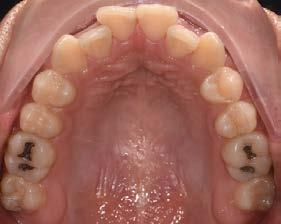

11, 12 y 13 mediante técnica CAD/ CAM, en su versión HT, color A2. Por otro lado, las otras 2 coronas de los OD 21 y 22 fueron confeccionadas con disco de zirconia Zahndent en tono A2. Estas fueron puestas a prueba mediante la aplicación Adobe Photoshop, con ayuda de una fotografía de las coronas tomada antes de su cementación definitiva, y una segunda medición con las coronas ya cementadas, únicamente se realizó el análisis en los OD 11 Y 21, los cuales fueron cementados con cemento translucido Multilink Speed de Ivoclar Vivadent, se tomaron fotografías con cámara profesional Cannon T8 y lente macro 100mm. Es importante mencionar que decidí utilizar cemento dual translucido para evitar alteración en el color de las coronas ya cementadas, con el fin de obtener mediciones puntuales de color y determinar las cantidades de pigmento que hay en cada corona mediante un fondo negro y así poder corroborar que se logró un buen mimetismo. El tiempo estimado para el procedimiento fue de 5 citas.

Se realizó la medición del color de las coronas mediante una fotografía en formato RAW en fondo negro (Figura 2).

Se realizó un segundo análisis con las coronas ya cementadas en boca, únicamente de los incisivos centrales superiores, ya que uno fue confeccionado con disilicato de litio y el otro con zirconio. En este caso obtuvimos como resultado en la corona de disilicato de litio: del color rojo: 172, del color verde: 148 y en cuanto al color azul: 123. En la corona de zirconio obtuvimos del color rojo: 171, del color verde: 143, y del color azul: 119; en la escala de 0 a 255 que arroja la aplicación de Adobe Photoshop.

Se muestra un análisis comparativo de las coronas de los incisivos centrales, las cuales fueron confeccionadas, una con disilicato de litio, y la otra con zirconio.

Figura 3. Coronas ya cementadas.

Tabla 2. Análisis de las coronas ya cementadas. Se muestra un análisis comparativo de las coronas de los incisivos centrales, las cuales fueron confeccionadas, una con disilicato de litio y con zirconio.